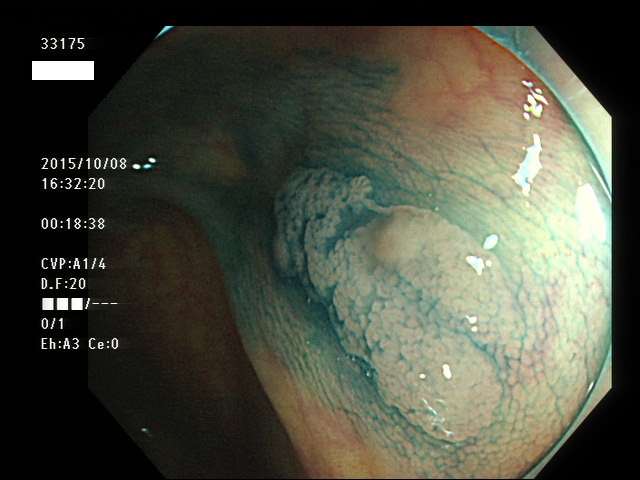

上記100名より抽出した平坦・陥凹型腺腫(=癌化の危険が高いが見落としやすい病変)の内視鏡写真